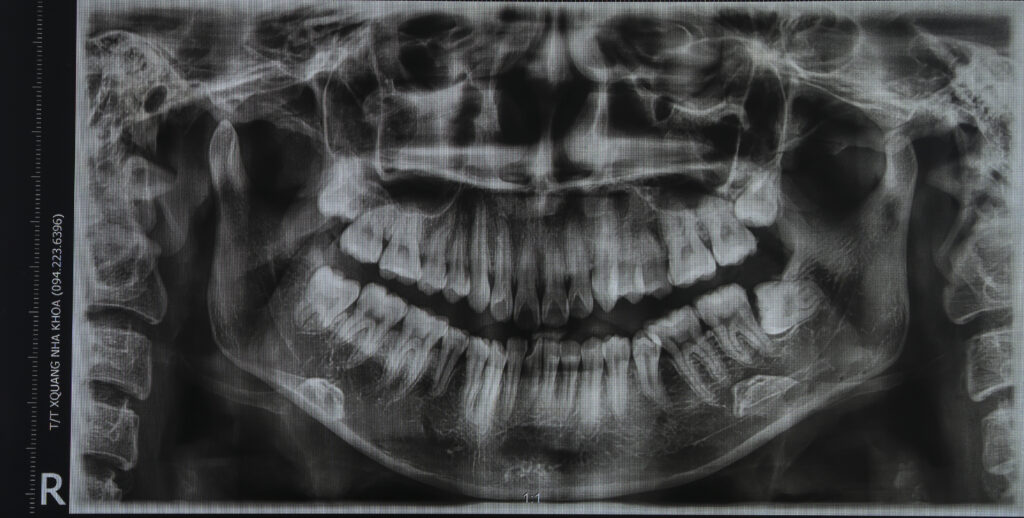

Chẩn đoán trước điều trị: sai khớp cắn hạng II, mặt hô, khớp cắn sâu. Chỉ định niềng răng nhổ 4 răng số 4 để kéo lùi nhóm răng cửa giảm hô tối đa. Có sử dụng neo chặn tuyệt đối bằng minivis chỉnh nha.